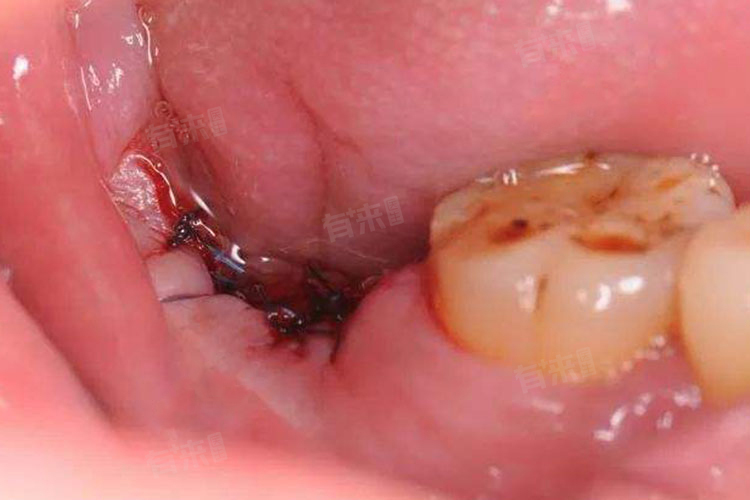

- 干槽症牙洞最显著的特点之一是牙槽窝的空虚状态,正常情况下,拔牙后的牙槽窝会逐渐被血凝块填充,促进伤口的愈合。在干槽症患者中,拔牙窝内的血凝块往往脱落或未能有效形成,导致牙槽窝呈现空虚状态。这种空虚不仅使得牙槽骨直接暴露于口腔环境中,还增加了细菌感染的风险。

- 除了空虚状态外,干槽症牙洞还常常伴有坏死物的覆盖,这些坏死物可能是由拔牙过程中产生的创伤、细菌感染或术后口腔卫生不良等因素导致的。覆盖在牙槽窝壁上,形成一层厚厚的坏死层,用探针触及时会感到尖锐的疼痛感,这些坏死物的存在进一步加剧了牙槽骨的破坏和退化。